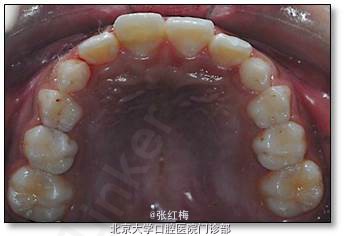

11牙冠龈1/3折断,牙髓暴露约6×1mm2,灰紫色,略有增生,叩(±),不松,龈未见异常,

21牙冠龈1/3釉质横形隐裂,叩痛(-),不松,冷测同正常对照牙,龈未见异常;

11、21正中牙合及前伸牙合未见明显牙合创伤;

12、22、32、31、41、42叩痛(-),不松,冷测同正常对照牙,龈未见异常

处理:11去旧充填体,11及断片牙体预备(颊侧备斜面,髓腔备固位形,舌侧备排溢道),one-coat bond+纳米树脂粘接断冠,调牙合,抛光。

治疗后六个月复查

检查:11粘接断冠完好,叩(-),不松,龈未见异常,冷测有感觉,无疼痛;X线:11根 尖继续

形成中,根周膜清晰

21叩(-),不松,龈未见异常,冷测同正常对照牙。